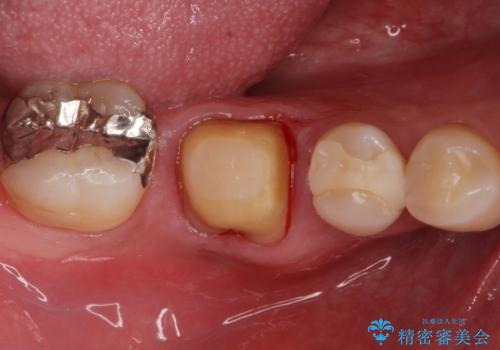

歯茎が腫れた。ジルコニアクラウンやりかえ。

- メンテナンスで来院された患者様です。

歯茎が腫れたとの事で歯の神経が失活していたので精密根管治療を行い、ジルコニアクラウンで治療を行いました。

神経が失活しているので痛みは感じにくいですがこのまま放置をしてしまうと骨が溶けたり痛みが出たりします。

このように歯茎にニキビみたいな物が出た場合、あるいは存在する場合すぐに歯科医院に相談することをおすすめします。